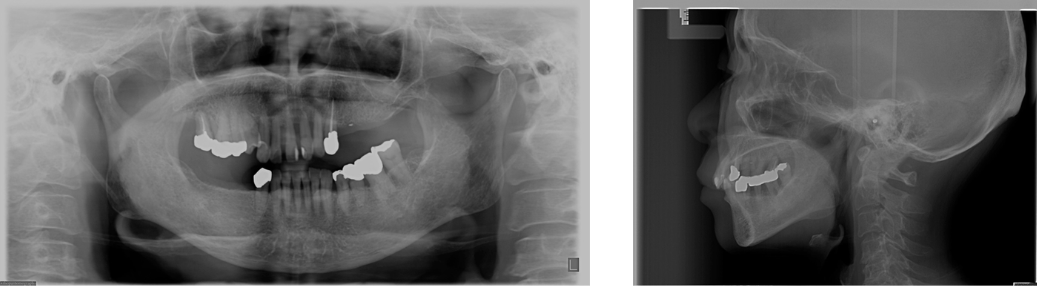

上顎、下顎の欠損のインプラント治療の症例(うえだ歯科)

| 主訴 | 全顎治療希望、歯が無いので噛みずらい。定年で時間の余裕出来たので、インプラントで治療して欲しい。 |

| 治療内容 | プラークコントロール不良なため歯周治療を行い、残存歯を極力温存し、欠損部インプラントを施し咬合再構成を行う。 プロビジョナルレストレーションによる咬合関係を模索した後、全顎にわたりセラミックによる補綴治療、その後メインテナンスに移行 |

| 治療費 | 6,470,000円(税込)(インプラントすべて含む) |

| 治療期間 | 1年6ヶ月 |

| 治療回数 | 72回 |

| 想定されたリスク | 食いしばり(パラファンクション)によるセラミックの破折、歯の破折 |